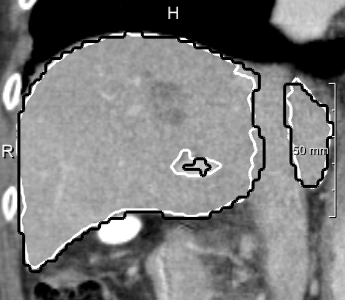

Example segmentations of the 2D U-net ensemble (2 mm) are illustrated in 3. Contour precision is limited by the resampling, but the model nicely excludes the vena cava and large hilar vessels much like in our training set. This hinders comparison against the state-of-art, since the reference masks from the SLIVER07 challenge (dashed in 3, right) partially include these vessels.

In most cases, the purely slice-wise application of the 2D U-net (dashed contours in 4) does not show any comb artifacts in orthogonal views. However, the ensemble classifier (solid contours) performs significantly better when the appearance is severely abnormal and 3D context is needed. In some cases, it locally performs worse, but has an overall better volumetric overlap (Wilcoxon signed-rank test, ). The ensemble models performed significantly better than the purely 2D transversal model on the same voxel size.